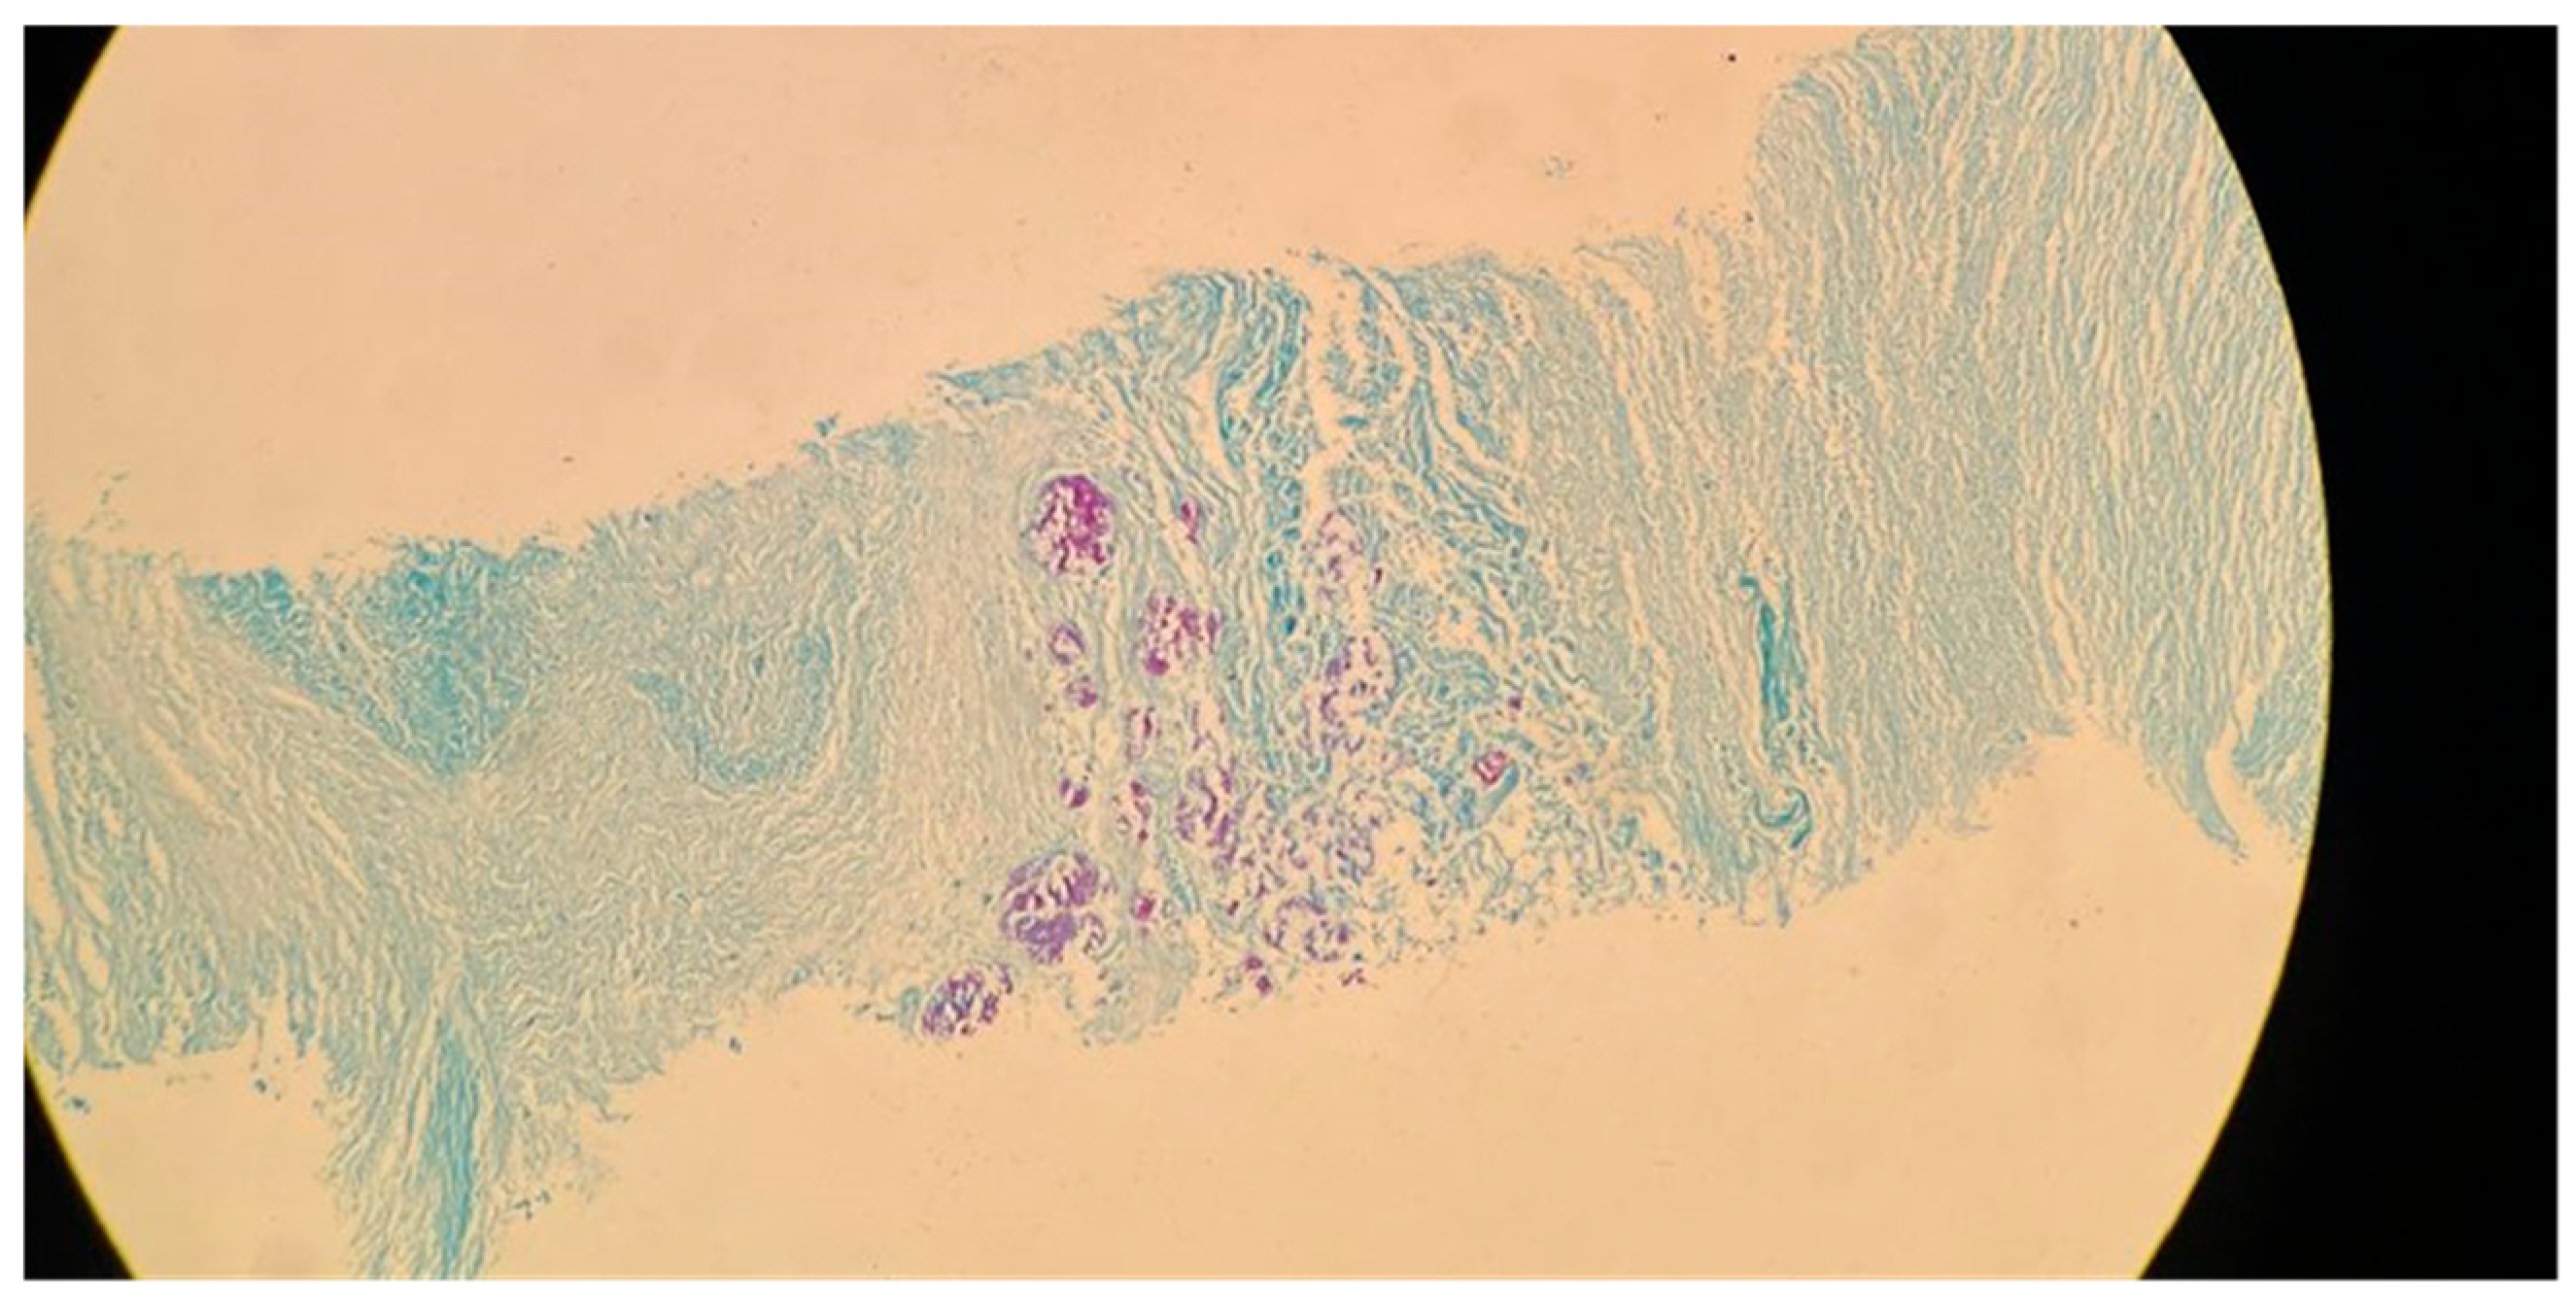

Figure 3. Acid-fast bacillus (AFB) staining of a sputum smear from the same patient referenced in Figure 2, demonstrating numerous acid-fast bacilli (red rods) against a blue background (100× magnification).

M. tuberculosis infection often leads to injury to the pleura. This includes the thickening and fibrosis of the pleura, and in many of these cases, patients further form calcification. About 40.9% of patients with fibrosis form these calcifications, as demonstrated in a CT-based study by Deshpande et al. [9]. The presence of fibrosis often results in decreased lung capacity on one side of the chest. This can be due to the cavities that form within the lungs as a result of the infection. In patients who had a single cavity in their lungs, fibrosis was found 100% of the time and calcification 80% of the time. In addition, 90% of these single cavities were found in the upper lobes of the lungs [9]. Upper lobe damage to the lungs can be seen in Figure 2. Further evidence of the presence of M. tuberculosis can be observed in Figure 3, in which many acid-fast bacilli are shown. The consistent presence of fibrosis and calcification in these cases suggests prolonged infection. This represents the host’s attempt to contain the mycobacterial focus. Fibrosis may contribute to disrupted lung structure and functional impairment of the lung, while calcification often marks the healing or inactive phase of a granulomatous lesion.